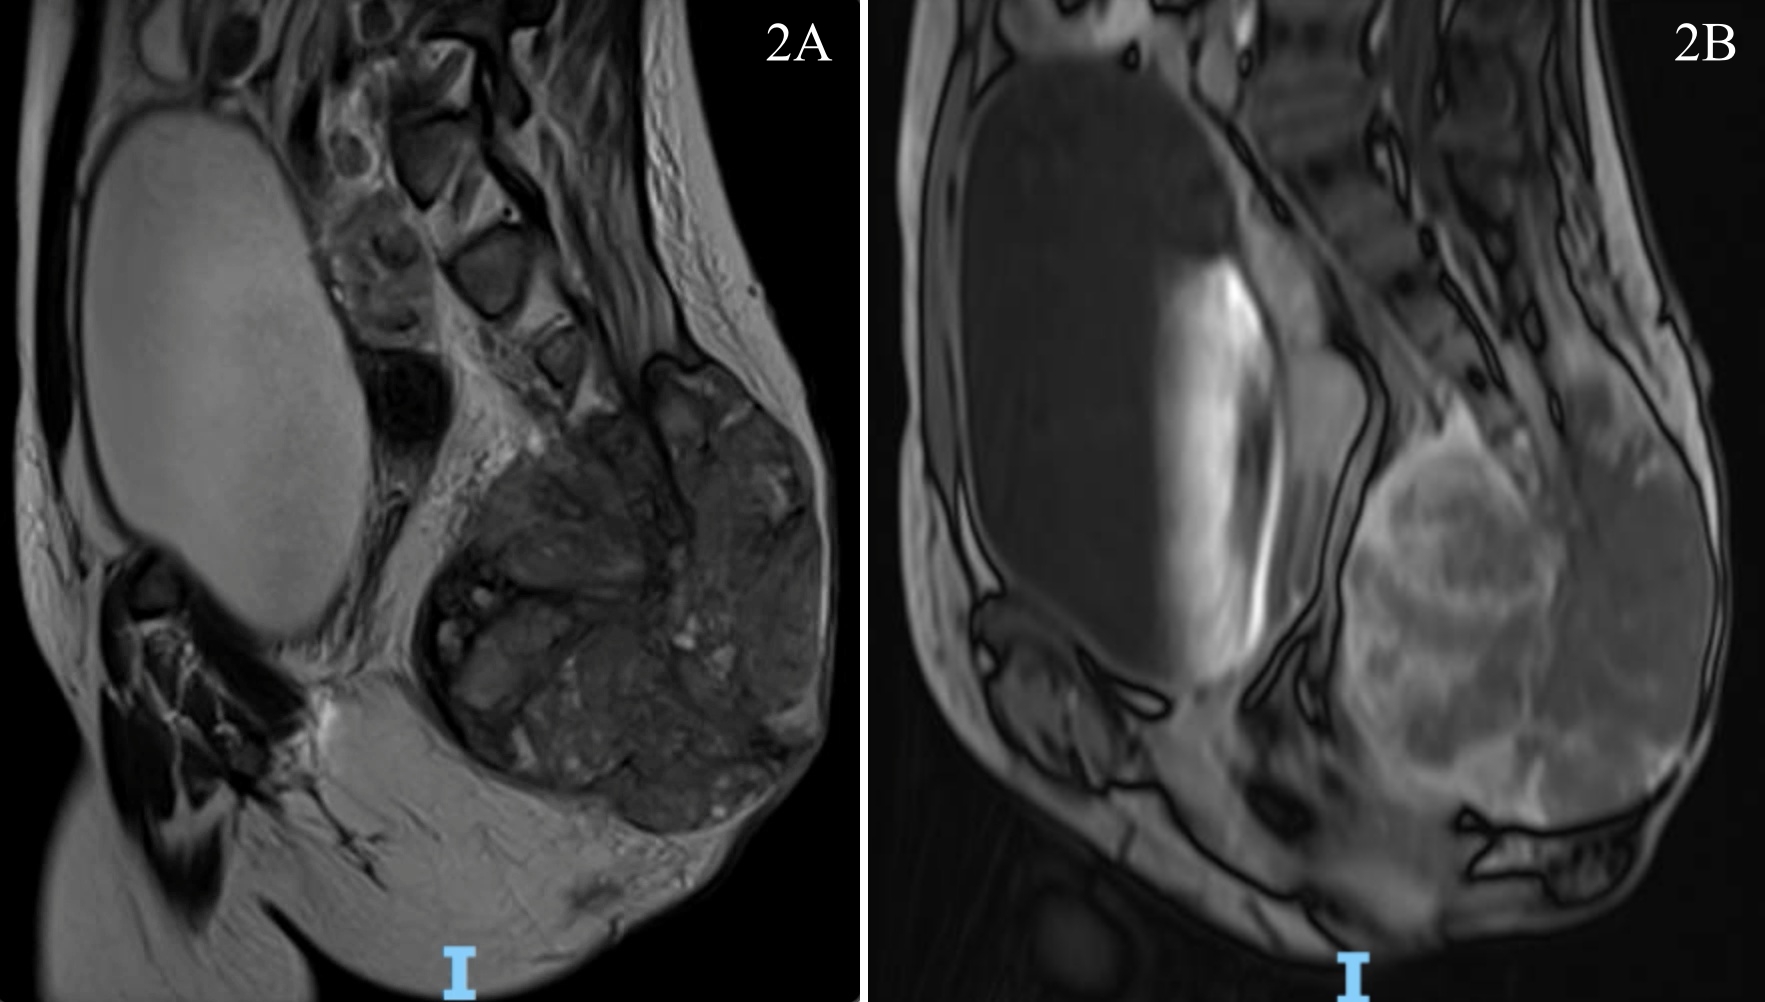

Case Report: 13 y-o girl transferred with a huge mass lesion in the lumbosacral area. In the primary hospital,she was submitted to a biopsy, whose anatomopathological report showed chordoma. The patient started with pain in the lumbosacral region a year ago, which rapidly evolved to a significant bulging in the area, pain in the posterior region of the left lower limb, urinary retention, and difficulty in walking. A surgical approach, both anterior and posterior, was performed en block resection of the tumor. During the procedures, there was evidence of metastatic dissemination to the ovary and peritoneum. The pathological examination confirmed the initial diagnosis. Due to the late recognition of the condition and the fast evolution of the disease, there was not enough time to perform adjuvant radiotherapy and the patient died.

Discussion: From notochordal remnants, chordoma manifests in less than 5% of patients in the first two decades of life and is occasionally found in the sacral region, but rarely with metastatic dissemination at presentation. These patients open up with the manifestation of local pain and, when not diagnosed early, progress with bulging of the sacral region and tumor dissemination. Management is based on primary resection, for the complete removal of the lesion, followed by radiation therapy.